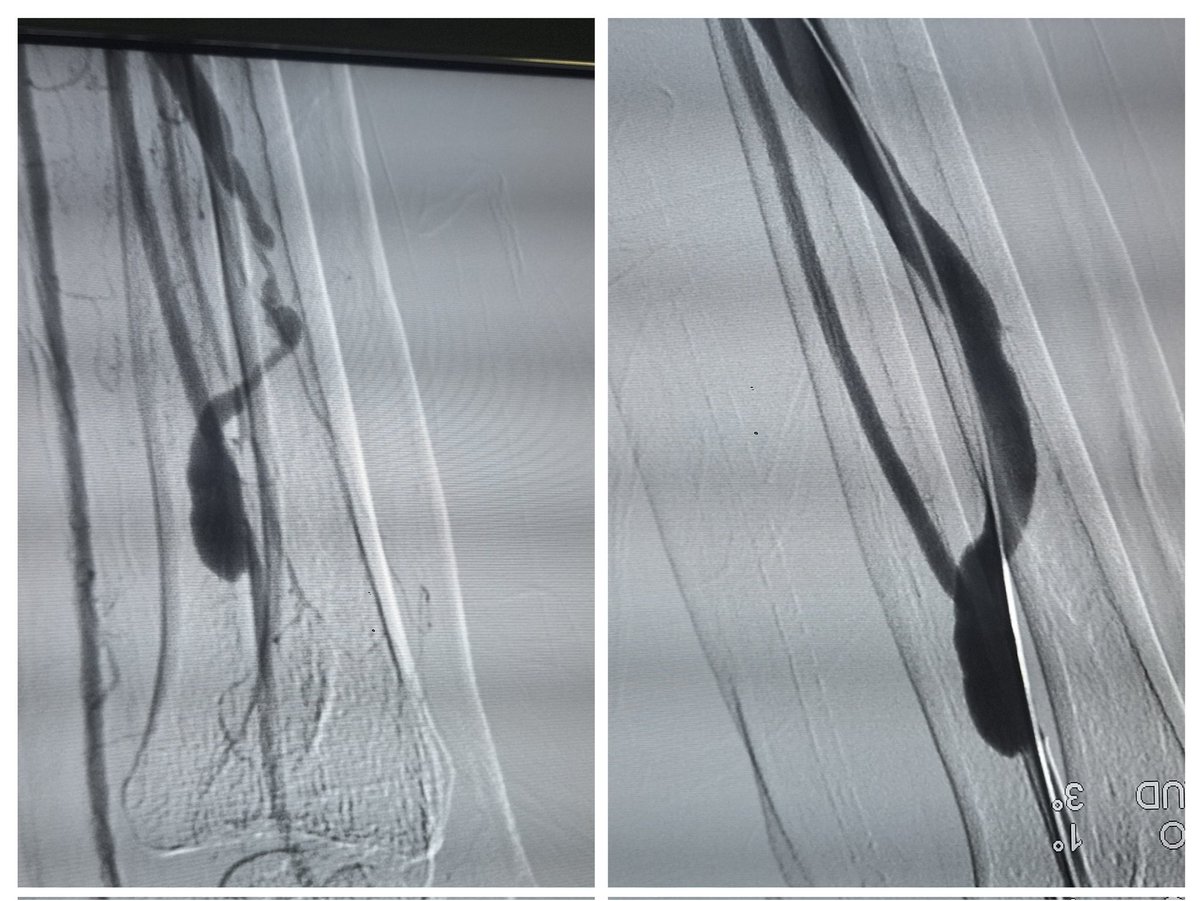

In the quest for early transplant, don’t forget the lifeline — vascular access. This patient was a week away from transplant, with only a catheter in place which was removed without a plan . Access planning is equally important #AccessEd @VascularForum #MedTwitter #Nephrology

vascularsrgn's tweet image. In the quest for early transplant, don’t forget the lifeline — vascular access. This patient was a week away from transplant, with only a catheter in place which was removed without a plan . Access planning is equally important